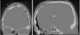

Meningoencephalocele

Encephalocele is a neural tube defect characterized by sac-like protrusions of the brain and the membranes that cover it through openings in the skull. These defects are caused by failure of the neural tube to close completely during fetal development. [Source: Wikipedia ]